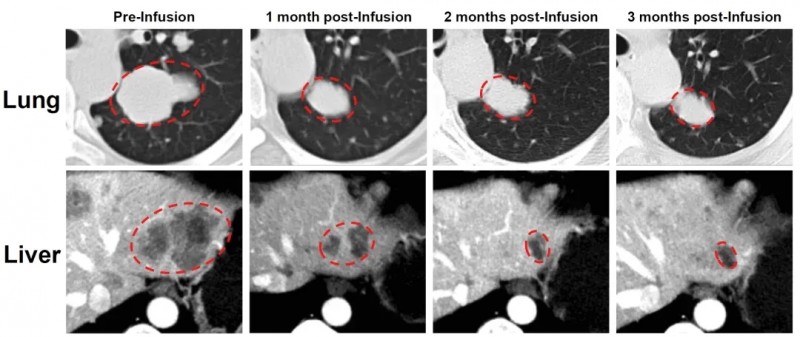

典型案例中,一位卵巢子宫内膜样癌患者入组前经化疗、PARP抑制剂等5种全身治疗,病情仍恶化。在接受GC203TIL细胞治疗后,奇迹正式上演:肝脏和肺部转移灶显著缩小,次月复查靶病灶缩小66%,达部分缓解(PR)标准,为患者重燃生存希望!

▲图源“JUN CELL官网”,版权归原作者所有,如无意中侵犯了知识产权,请联系我们删除